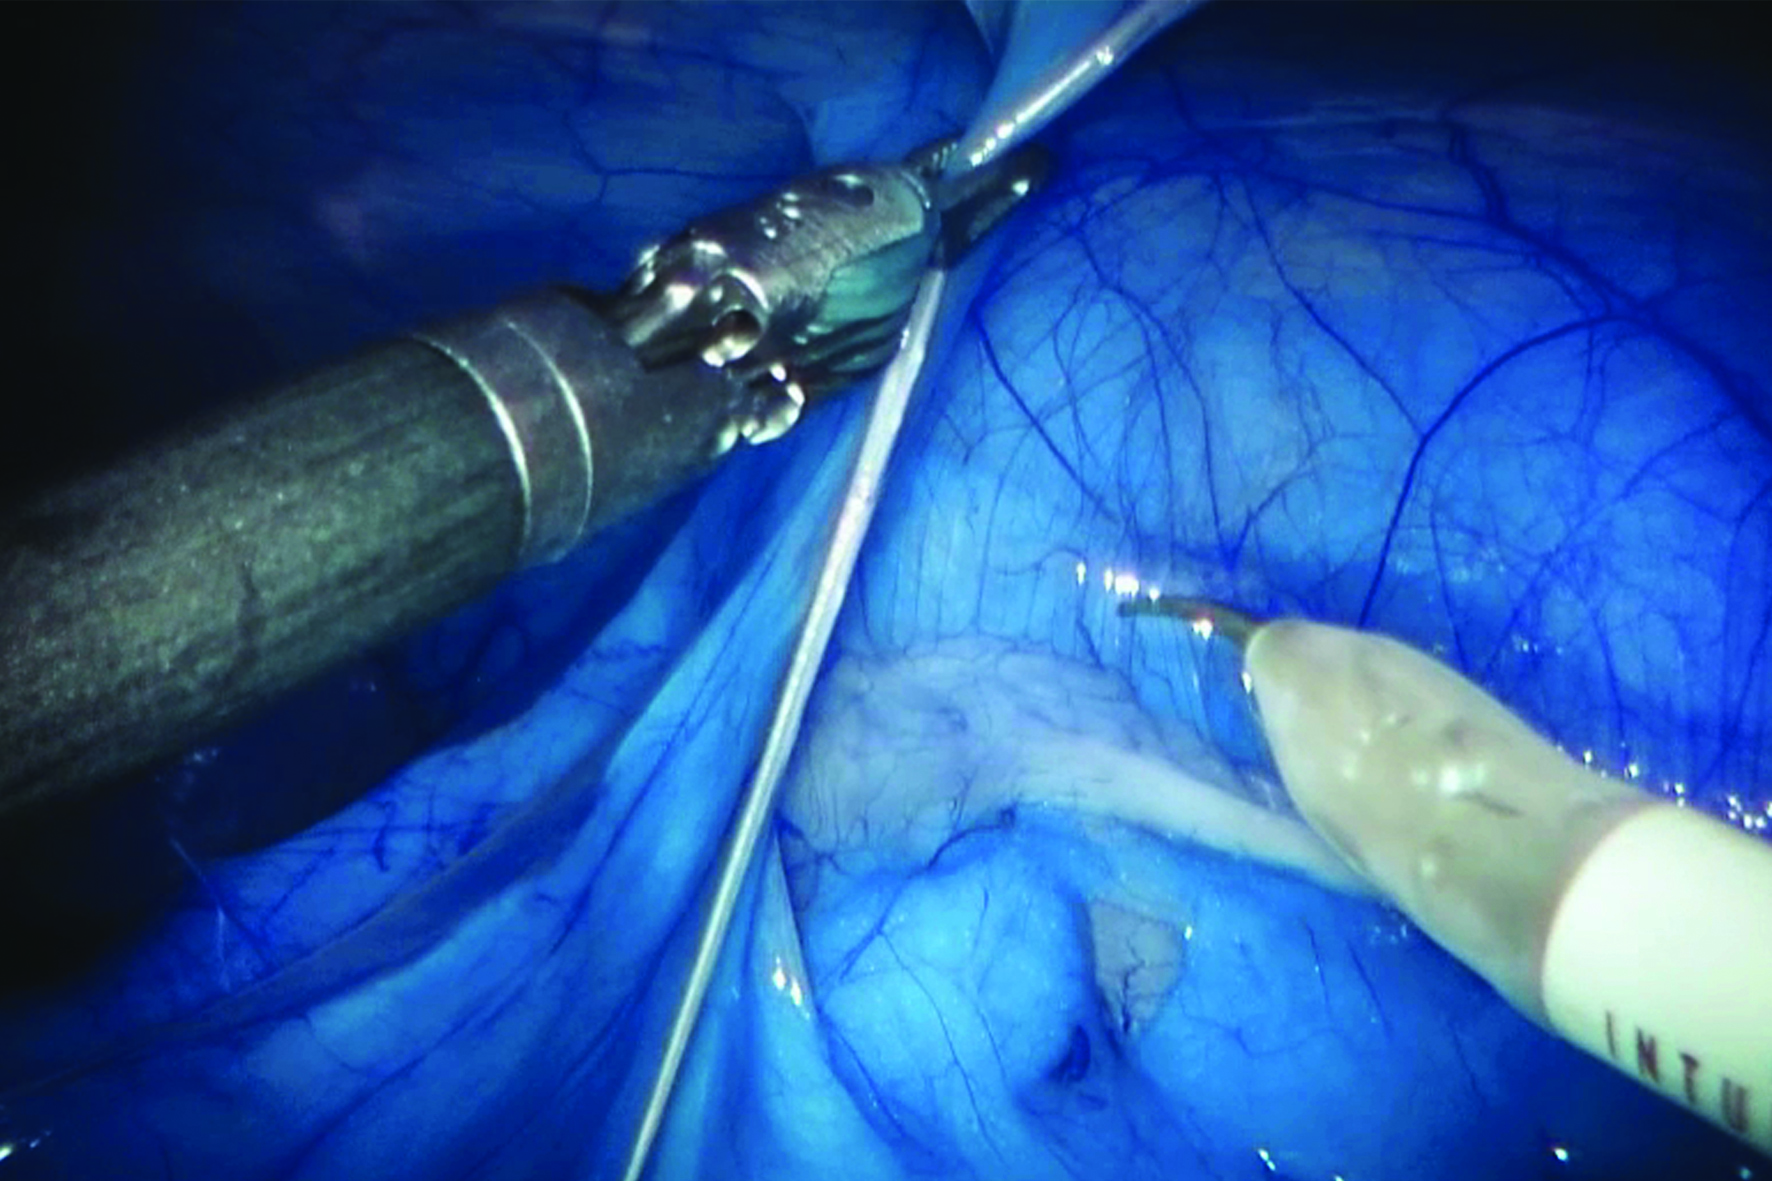

Dit laatste deel van Ancarani’s trilogie speelt zich af in een operatiekamer, waar een wonderlijke reis door het lichaam wordt gemaakt, uitgevoerd door robotarmen met de chirurg achter een soort joystick. Het geheel roept sciencefictionachtige associaties op met Fantastic Voyage (1966). Ancarani brengt de hele operatie, wonderschoon uitgelicht (zonder bloederige effecten), als een duizelingwekkende choreografie met minuscule precisie in beeld, met bijzonder spannende soundtrack.